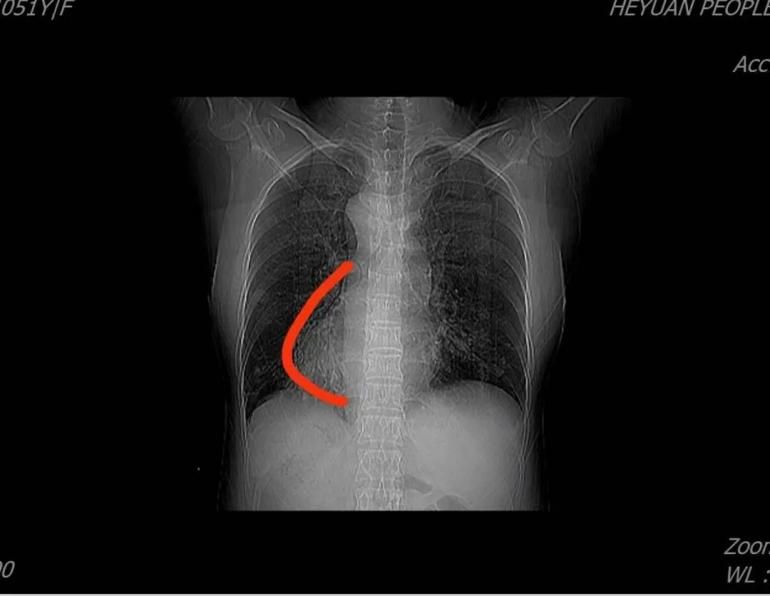

患者周某某,女,51岁,因“反复咳嗽、咳痰30余年,加重5天”入住我院呼吸与危重症医学科,胸部CT示双肺支气管扩张、右位心;入院诊断:支气管扩张症并感染。罗少华主任医师查房分析患者病情指出,患者双肺支气管扩张,右位心伴全内脏转位,需考虑罕见病——“卡塔格内综合征”,结合后续的完善鼻窦CT:双侧筛窦、上颌窦、蝶窦、右侧额窦炎,符合“卡塔格内综合征”的诊断标准。经规范治疗,患者病情好转,予做好健康宣教后出院。

X线影像示右位心表现